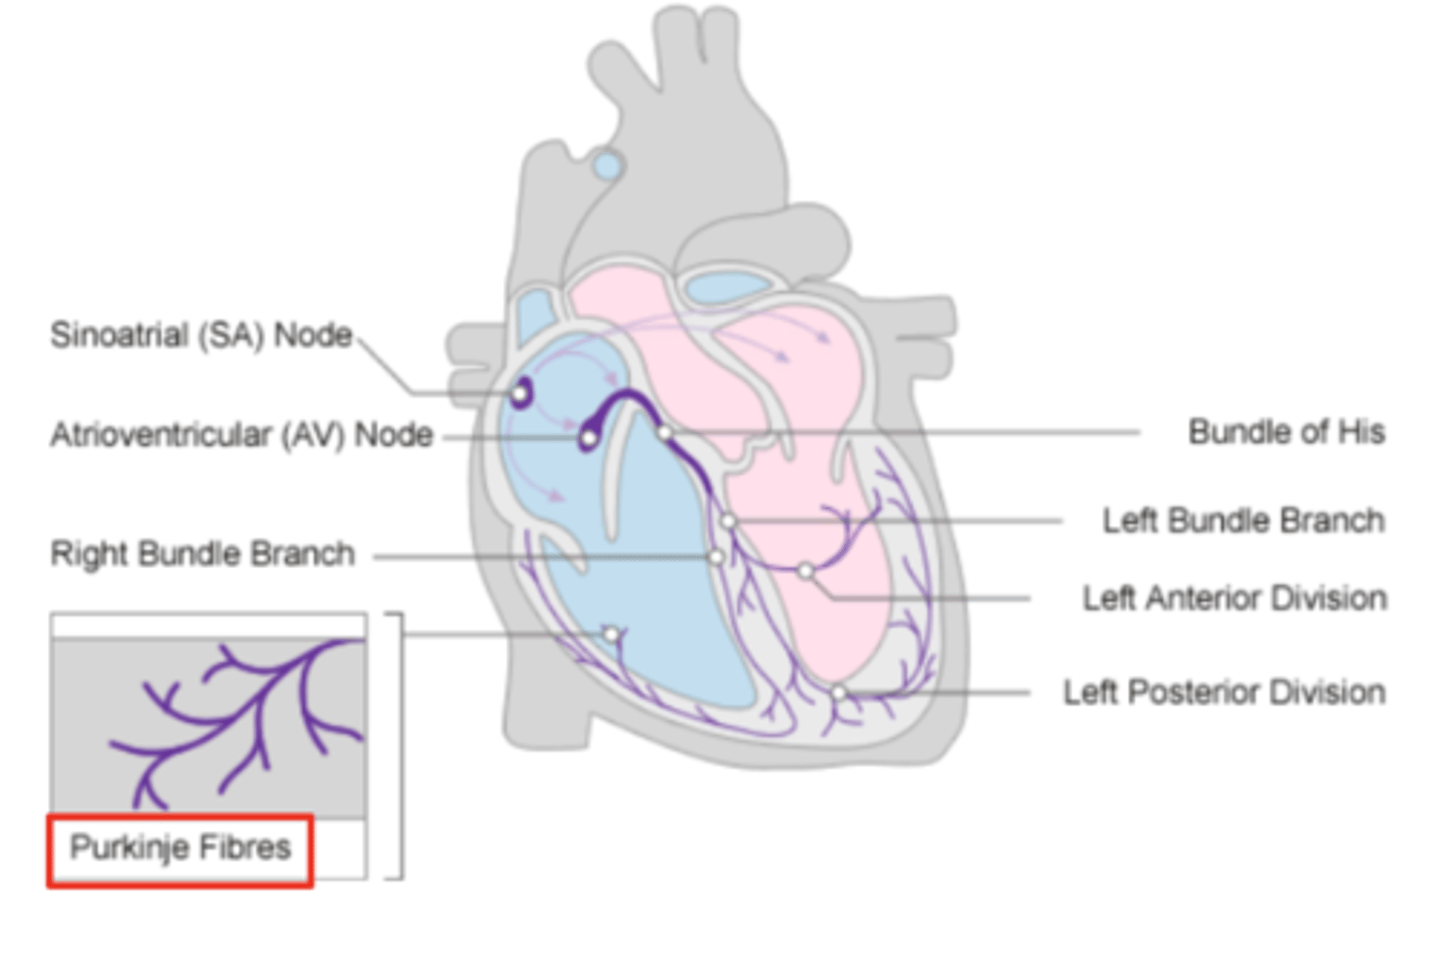

What allows the heart to contract by itself?

The heart possesses a specialized conduction system that gives it the autonomous capacity to contract, allowing it to pump by itself in a correct buffer.

What are the two conduction nodes of the heart conduction system?

. SA node (sinoatrial node)

. AV node (atrioventicular node)

What is the function of the sinoatrial (SA) node?

Pacemaker of the heart

Where is initiated the contraction of the SA node?

SVC (Superior Vena Cava)

passing through the atrium to the AV node

Where is the SA located?

upper wall of the right atrium,

at the junction where the superior vena cava enters

Where is the atrioventricular (AV) node located, and what follows it?

At the level of the atrioventricular septum,

AV node is followed by?

Bundle of Hiss that divides into two branches

Where does Bundle of Hiss ends?

Purkninje fibers

Describe the propagation of waves in the conduction system ?

. SA node sends the initial wave

Passes through the walls of the atria

. Ends at the AV node in the AV septum

. Travels along the Bundle of His

. Reaches Purkinje fibers in the walls of the ventricles

What role does the moderator band play in the conduction system?

Allows the wave to reach the papillary muscles, inducing their contraction simultaneously with that of the ventricles.

REMEMBER: PAPILLARY MUSCLES ACT THROUGH THE CHORDAE TENDINAE TO CONTROL THE TRICUSPID AND MITRAL VALVES.

What is the significance of the Bundle of His in heart conduction?

Branching to the right and left to ensure coordinated contraction of the ventricles.

What are the Purkinje fibers, and what is their function?

specialized conductive fibers in the walls of the ventricles that

facilitate rapid transmission of electrical impulses,

ensuring efficient and synchronized ventricular contraction.

How does the AV node contribute to heart rhythm?

Delays the electrical impulse from the SA node,

ensuring that the atria contract fully to transfer blood to the

ventricles before the ventricles contract.